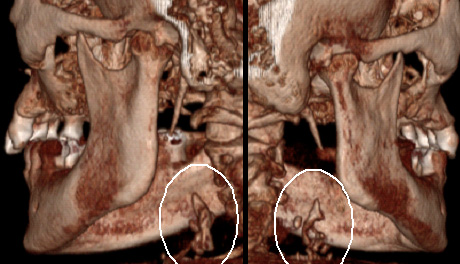

Cone-Beam Computed Tomography (CBCT) is an advanced 3D imaging modality that plays a transformative role in treatment planning. When properly acquired and systematically analyzed, CBCT data significantly enhances patient care. It is essential for clinicians to evaluate all anatomical structures captured in the scan, rather than focusing solely on the region of interest. A comprehensive interpretation of the entire dataset is critical for developing an accurate and effective treatment plan.

At Voxel Readers, we are a team of skilled, dedicated professionals devoted to extracting the maximum clinical value from your scans. We provide the highest quality CBCT data interpretation and support, ensuring timely, professional analysis to guide your decision-making process. Our secure, web-based platform is intuitive, user-friendly, and mobile-enabled. Once files are uploaded to our secure server, we analyze the data and provide a detailed report, including relevant images in PDF format. You will be promptly notified via email once the report is ready. Our interpretation services are completed within 3–4 business days.